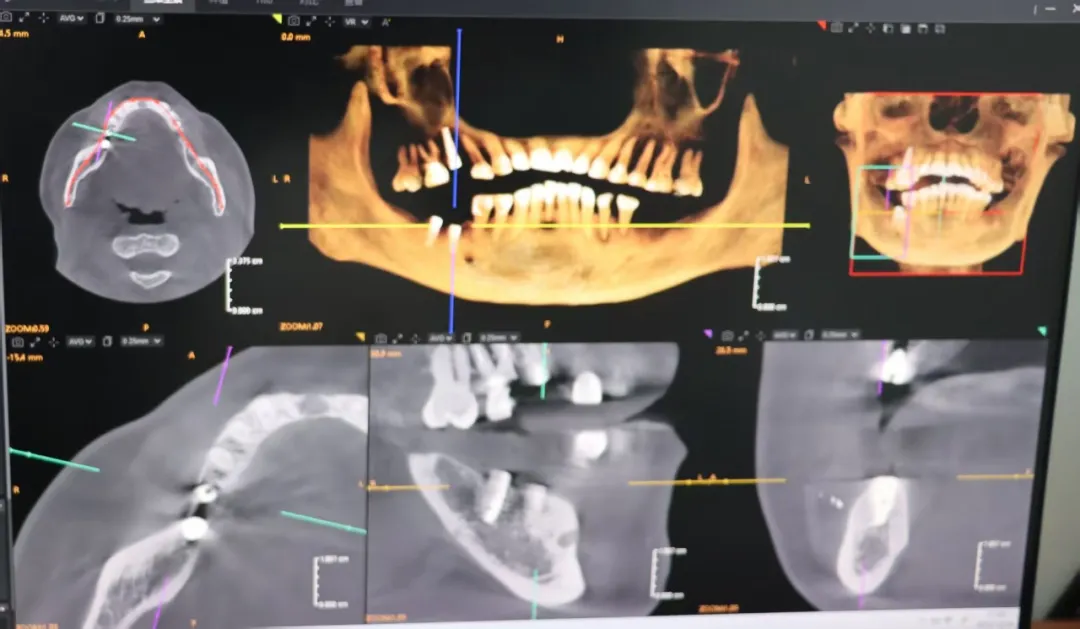

患者因右上下后牙缺失两年,影响咀嚼功能与生活质量。为彻底解决这一问题,患者到该院口腔科就诊。接诊医生进行了细致的口腔检查,并结合医院引进的先进口腔CT影像设备进行了全面评估。该设备能提供三维立体影像,清晰显示牙槽骨的高度、宽度、密度以及重要解剖结构的位置,为制定精准、安全的种植方案提供了关键依据。

手术由广西医科大学第一附属医院口腔科周进文医生指导并主操作。在局部麻醉下,周进文医生与该院口腔科团队紧密配合,为患者右上第五颗牙、右下第六、七颗牙的缺牙区,精准植入了三颗种植体。术后口腔CT复查显示,种植体植入位置、方向、深度均达到理想状态,为后续牙齿修复奠定了坚实基础。

术后口腔CT影像图